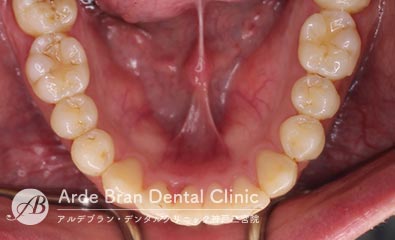

- 鋏状咬合/シザースバイト(20代男性 治療期間10カ月)

- 奥歯のかみ合わせと前歯のがたつきを治したいとの事でご来院されました。なるべく目立たない装置で固定式の装置での治療をご希望されたので、ハーフリンガル矯正にて治療を行いました。奥歯がすれ違って咬んでいる場合はご本人も気づいていない事も多いです。ただこの状態を放置しておくと、歯に大きく負担がかかり歯の寿命が短くなります。今回は上顎の口蓋にインプラントアンカーを植立し、外側に倒れた上顎の奥歯を内側に入れました。患者様より、長年歯並び歯並びが気になっていたので、これからは歯を見せて笑えるのが楽しみです。とのお声を頂きました。

- 治療前

- 治療後

| 装置名 | マルチブラケット装置(ハーフリンガル矯正) |

| 抜歯非抜歯 | 親知らずのみ抜歯 |

| 治療期間 | 10カ月 |

| 費用 | ハーフリンガル矯正83万円+TAX 顎間ゴム500円×数個 |